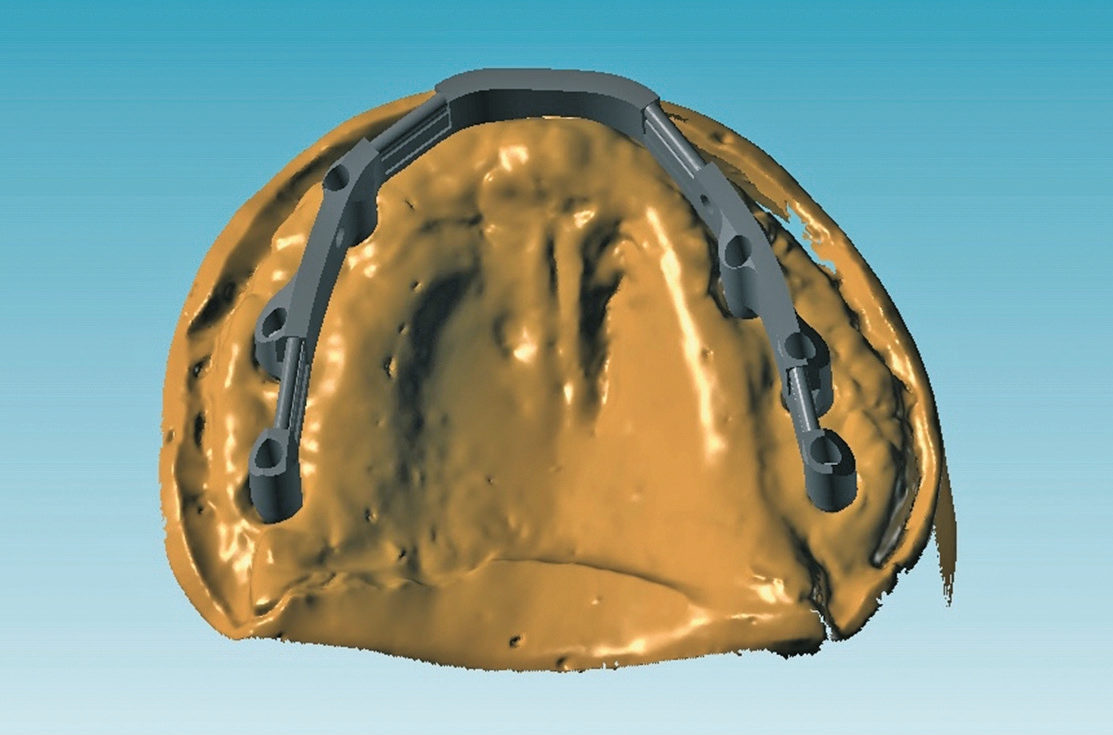

Die zum Fräsen des Steges benötigten Daten wurden zusammen mit dem Meistermodell, dem Gegenbiss und der für die Ästhetikanprobe verwendeten Zahnschablone an ein zentrales Fräszentrum (ATLANTIS™ ISUS, Dentsply Sirona Implants) übermittelt. Das Stegdesign wurde in Absprache zwischen dem CAD/CAM-Fräszentrum und dem Zahntechniker geplant (Abb. 15). Dabei erhielt das Labor den Designvorschlag per E-Mail, zusammen mit der erforderlichen Software (ATLANTIS ™ ISUS Viewer, Dentsply Sirona Implants). So konnte die Suprakonstruktion dreidimensional am Computerbildschirm dargestellt werden.